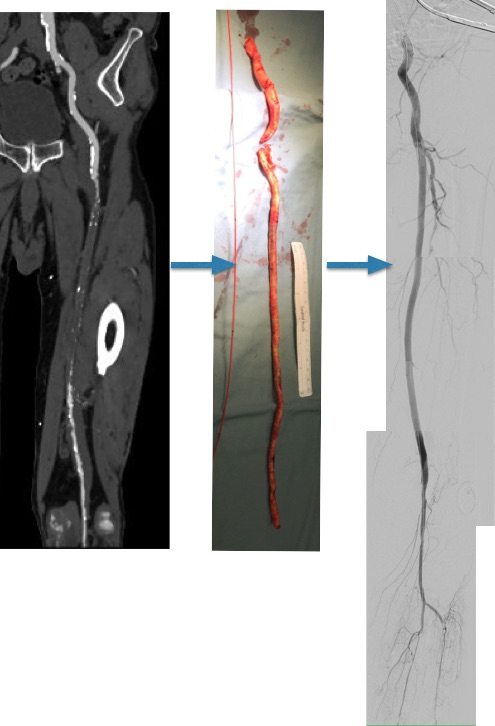

The patient is a 70 year old man who arrived with complaints of worsening claudication, worse on the left leg. He smokes over a pack a day. On exam, he only had femoral pulses, nothing was palpable below. PVR showed multilevel disease with an ABI of 0.42 on the left leg.

CTA was done showing that both his SFA and PFA were occluded, along with occlusion of his AT in the mid leg, and tibioperoneal trunk.

There is a reconstitution point on the PFA, and there is also SFA constitution. Looking at this, it was apparent to me that it would be possible to endarterectomize the whole of the iliofemoral and femoropopliteal system from a single groin incision, but the question being, would a profundaplasty be sufficient.

The CFA, PFA, and SFA were exposed as shown in my sketch at the beginning of the post. Wire access up and over from the right side allowed for secure control of the aortoiliac segment. The endarterectomy was started from the PFA reconstitution point and the CFA plaque was mobilized. The SFA plaque was transected in a proximal arteriotomy and the plaque was mobilized with a ring to its origin. The CFA plaque then was mobilized with the ring dissector over a wire (for security in case of rupture), up to the EIA origin and cut.

The distal SFA plaque was endarterectomized to the planned end point above the knee joint.

The specimen is shown below.

The arteriotomies were repaired with patches. The common iliac artery was stented to improve the flow. The SFA end point was managed with a stent, placed proximal to the first large geniculate collateral.

Completion angiograms show widely patent EIA, CFA, PFA, and SFA